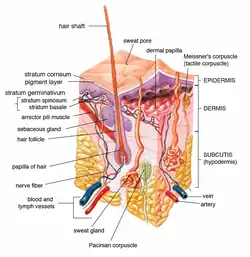

Microscopic image of the epidermis, which constitutes the outer layer of skin, shown here by the white bar | |

Epidermis and dermis of human skin

Epidermis and dermis of human skin Cross-section of all skin layers

Cross-section of all skin layers Illustration of epidermal layers

Illustration of epidermal layers Optical coherence tomography of fingertip